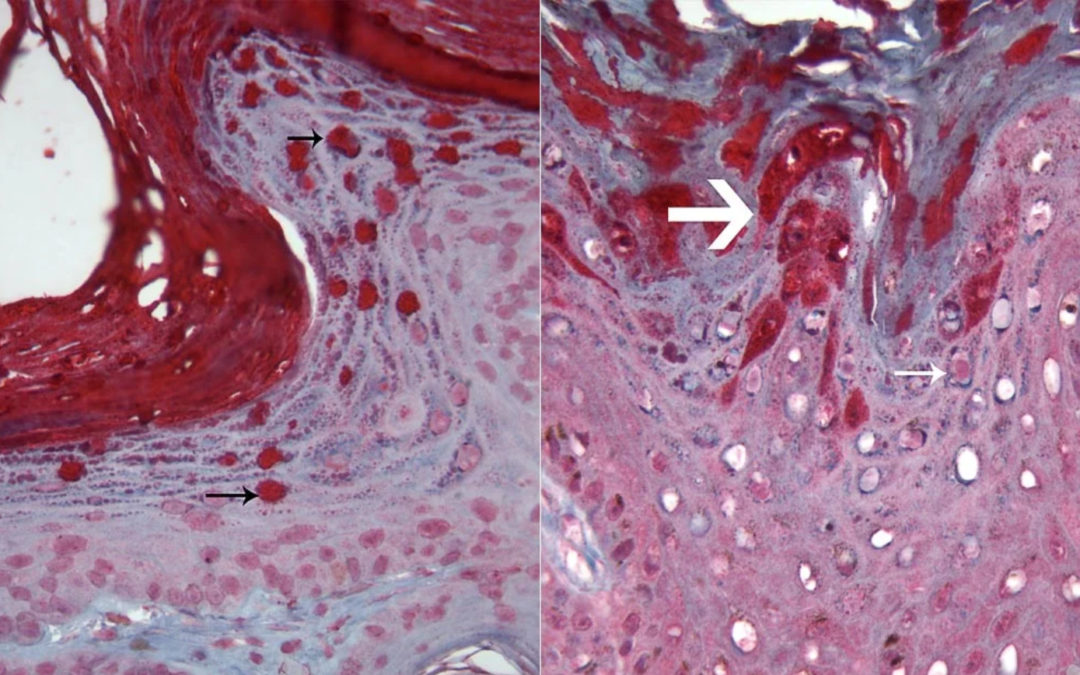

Autor: Berrocal, A. Definición de quiste: significa una estructura formada por una pared de origen epitelial, con una cavidad la cual puede estar vacía o tener un contenido( lumen) secretado por las células que componen su pared. Ver siguiente figura 1. Fig.1....